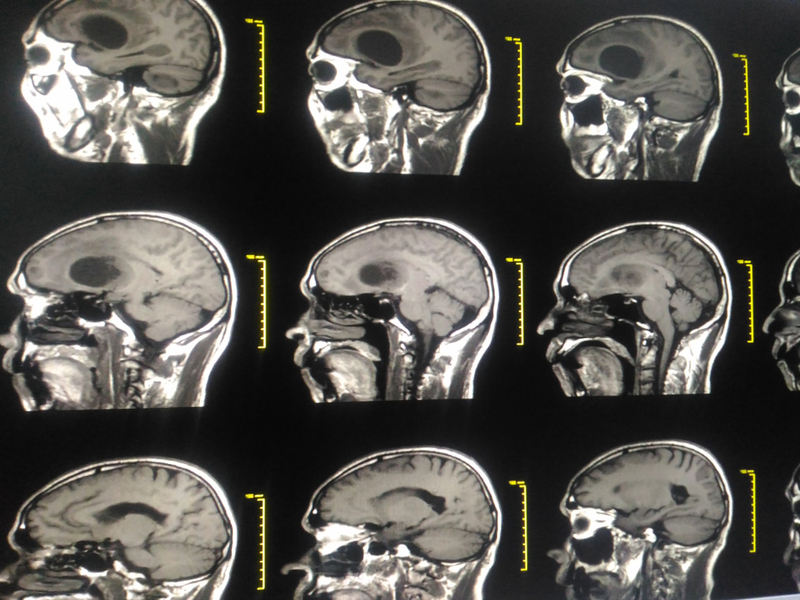

New drug shows promise in halting spread of brain cancer

Scientists have developed a novel drug that could block glioblastoma -- the deadliest form of brain cancer -- from spreading.